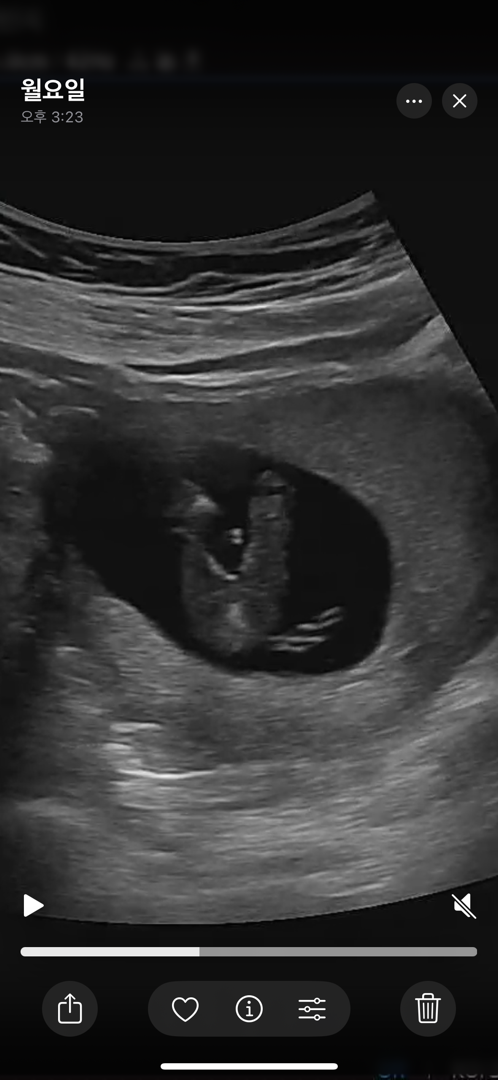

하얀건 탯줄 같고 딸 같아보여용

너 딸이니

하얀건 아니겠죵

하얀건 탯줄 아닐까요!!

저도 탯줄같아용

저희는 아들추정인데 몸에서 톡 튀어나온건 이래여!ㅎㅎ

하얀게 맞으면.. 테토남?!